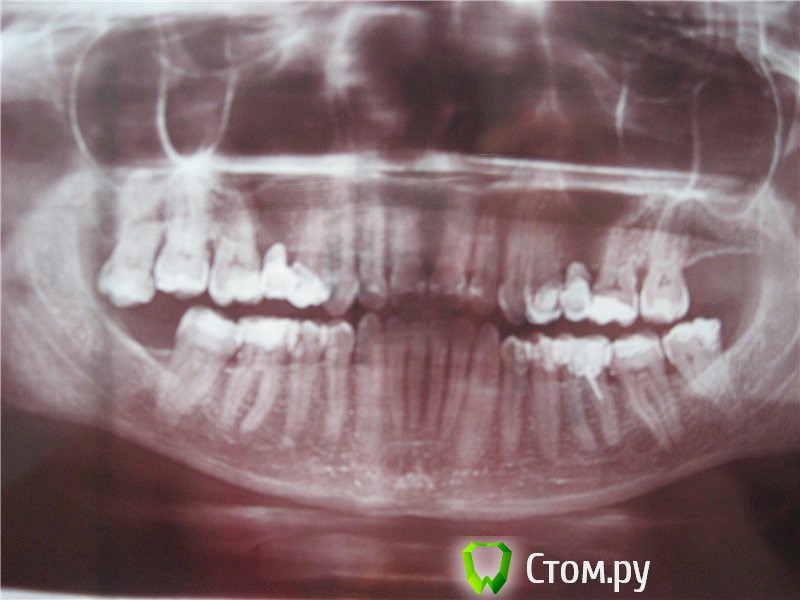

РитаТТа Опубликовано 5 августа, 2014 Поделиться Опубликовано 5 августа, 2014 (изменено) Не нравится состояние зубов. Есть желание поменять старые пломбы ( им более 10 лет) и коронки. С чего начать? Изменено 5 августа, 2014 пользователем РитаТТа Ссылка на комментарий

shishok Опубликовано 6 августа, 2014 Поделиться Опубликовано 6 августа, 2014 Для начала удалите 18 зуб(вверху справа зуб "мудрости").Он у Вас значительно сместился. 1 Ссылка на комментарий

РитаТТа Опубликовано 6 августа, 2014 Автор Поделиться Опубликовано 6 августа, 2014 Спасибо, хочу и нижний зуб "мудрости" удалить. Ссылка на комментарий